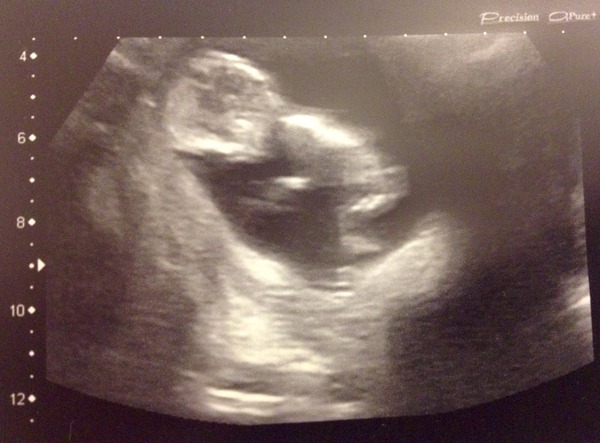

Runner05 · 16/02/2016 14:03

Back from the scan and all is well with the baby. He was jumping around like mad and determined to stay in the wrong position no mater how much the nurse poked him. In the end I kinda lifted myself into a bridge and wiggled my but to get him to shift, that did the job.

The neck fluid results were brilliant and I'll receive a call within 7 days if they have any concerns regarding the bloods (otherwise I'll get the all clear letter in 2 to 3 weeks).

Also the scan wasn't anywhere near as unpleasant as I expected, wasn't uncomfortable at all. The whole drink lots before you go thing was rubbish. I drank normally and had a wee before setting off.

The only not so good thing that came out of it was that she found a massive fibroid at the top of my womb (she kept telling me how impressively massive it is... Err, thanks? Hmm) it won't hurt the baby but I'm probably going to need consultant lead care and regular monitoring. Worse case scenario is that later in the pregnancy it will hurt (because the scar tissue won't stretch) and I might need a c-section but those run in my family anyway.

It does however explain why I look far more upduffed than I am and probably contributed to my morning sickness and my current discomfort. Oh well, at least now I know.

Anyway, here is my little potato playing an invisible jazz piano Wink